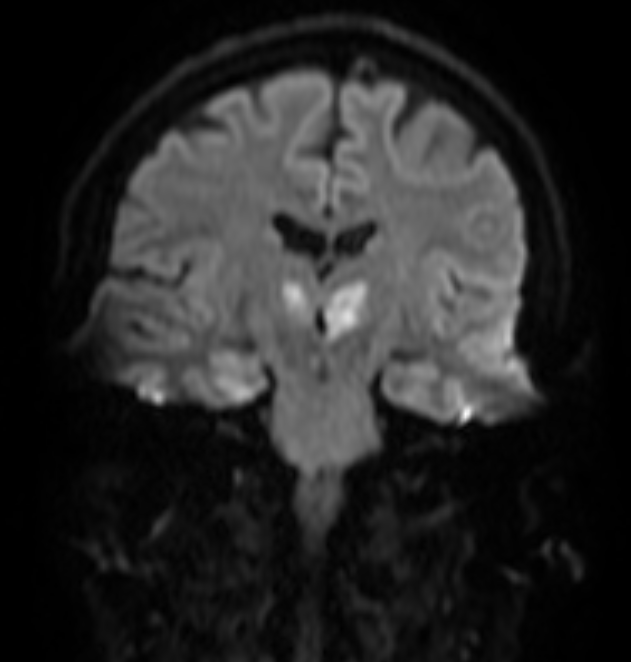

In neurology, the Artery of Percheron is a rare anatomical variant in which the blood supply for both medial thalamic nuclei arises from a single small arteriole at the top of the basilar artery, rather than from two individual arteries. An embolism or occlusion in the Artery of Percheron causes simultaneous bilateral infarcts. The medial thalami are necessary for maintenance of consciousness and attention, therefore artery of percheron stroke can cause an abrupt decrease in level of consciousness, confusion and drowsiness.